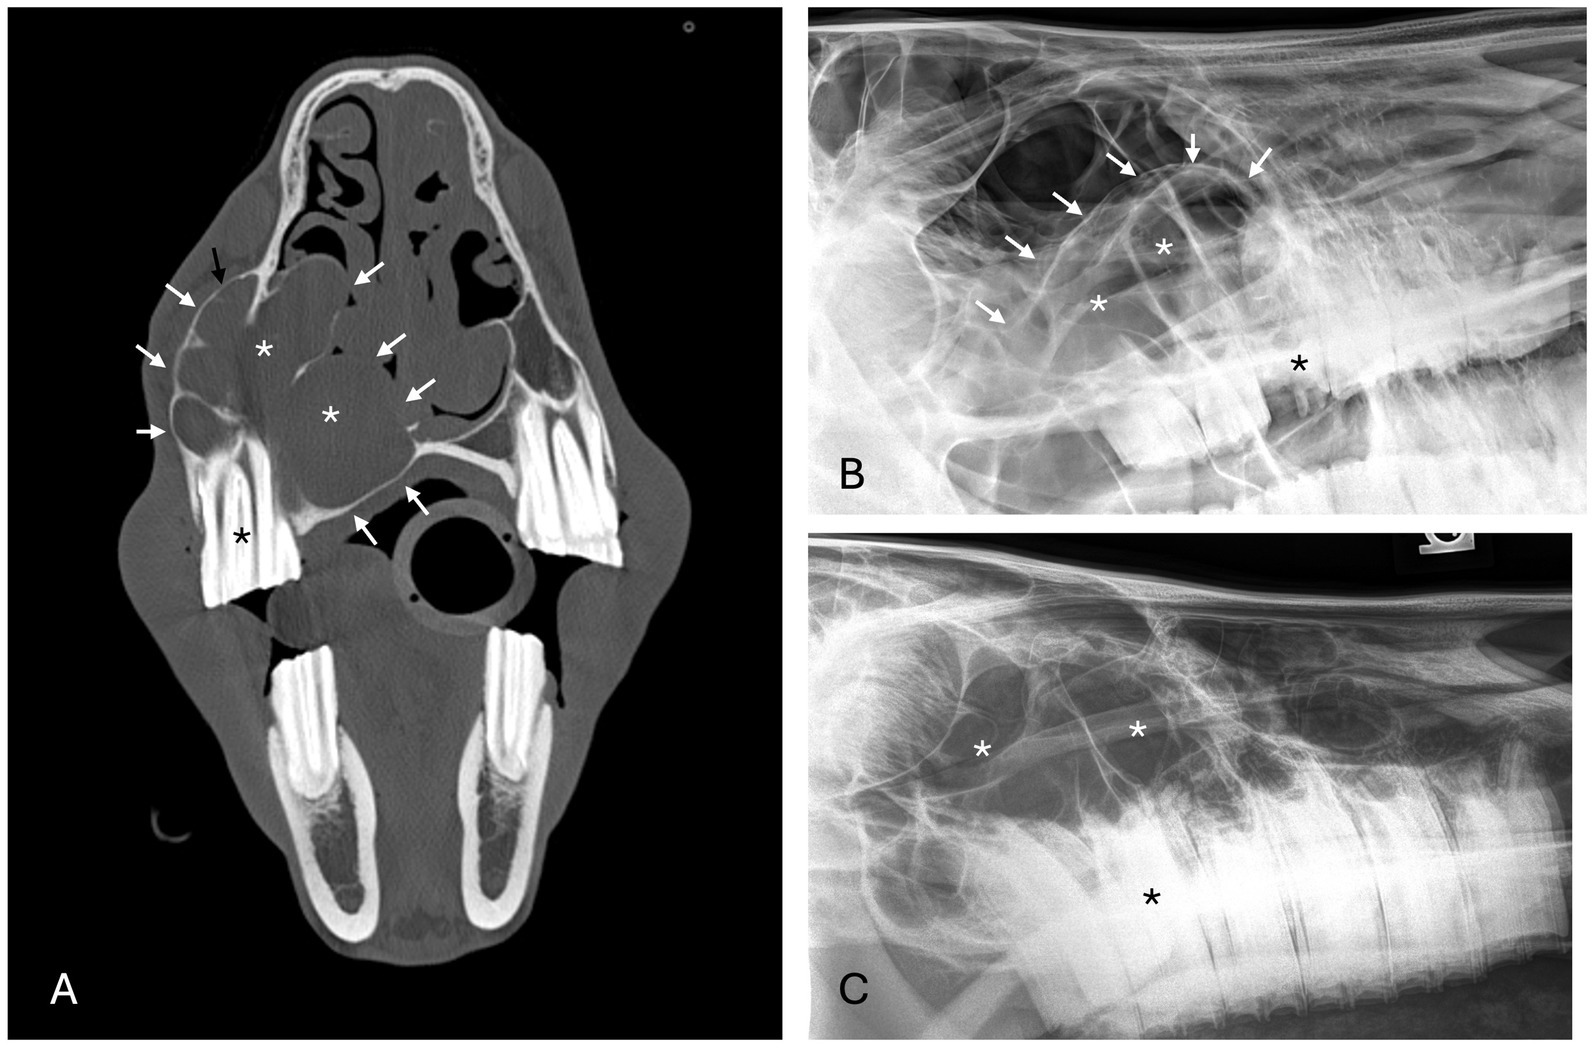

Histopathology supported the diagnosis for 6 bone cysts. The bone cyst lesions were histologically characterized by the presence of a fibrovascular stroma with embedded plates or thin trabeculae of well-organized or porous woven bone. All bone cyst cases had evidence of a pseudocystic lining that was defined as fibrovascular tissue of the luminal surface that contained macrophages and multi-nucleate giant cells and/or amorphous mineral deposits (Figure 6). Macrophages and multi-nucleate giant cells were present in 3/6 cases and 2/6 cases demonstrated macrophages with no multinucleate giant cells. Amorphous mineral deposits were present within the pseudocyst lining in 3/6 cases. Except for macrophages and multinucleate giant cells, no other inflammatory cells were present in the pseudocyst lining for 4/6 cases while mild lymphoplasmacytic inflammation was present in 2/6 cases.

Figure 6. Case 7 (A) Maxillary bone cyst from a young horse. A high magnification image of the luminal surface lacks an epithelial lining. Instead, fibrovascular tissue that faces the lumen has an irregular layer of macrophages (arrows), multinucleate osteoclast-like giant cells (double arrows), granular basophilic “chondroid-like” matrix (arrowhead), and erythrocytes from hemorrhage. Bar – 200um, HE stain. Case 10 (B) Mandibular bone cyst from an adult horse. A low magnification image includes the entire thickness of the lesion wall including a thin, compacted layer of reactive periosteal bone. Original cortical bone (approximated by the bracket) is thickened and replaced by reactive woven bone and fibrovascular connective tissue. The lumen contains hemorrhage. There is neither epithelium nor an organized cellular/debris layer along the luminal edge. Bar – 3 mm, HE stain.

If a cyst was associated with an erupted dysplastic and/or diseased tooth causing paradental inflammation, a radicular cyst was diagnosed. Radicular cysts were diagnosed in 3 cases. Two maxillary lesions had respiratory epithelium with one case demonstrating squamous metaplasia. The other rostral maxillary radicular cyst had well-differentiated stratified squamous epithelium with no keratinization although low cuboidal epithelial cells were noted in the biopsy sample from a third procedure after recurrence and persistence of the cyst (Figure 7). Mixed lymphoplasmacytic and neutrophilic inflammation was present to varying degrees in all samples.

Figure 7. Case 5, Maxillary radicular cyst. A high magnification image of the cyst lining has epithelium (bracket) supported by fibrovascular connective tissue with hemorrhage (hemorrhage is likely an artifact of surgical enucleation). The epithelium is transitional between non-keratinized stratified squamous and pseudostratified, although cilia are not evident. Bar – 100 um, HE stain.

No definitive histologic diagnosis was able to be made for both cases of unclassified inflammatory lesions. Case 6 was reported as inflammatory epithelialized periapical abscess or abscessed cyst that had tissue lining the bony cavity described as granulation tissue and fibrosis with chronic inflammation and partial epithelial lining. The epithelium was characterized as nonkeratinized stratified squamous epithelium (Figure 8). Case 12 was reported as an inflammatory pseudocyst with secondary edema, fibrosis and mild bone remodeling. No epithelial lining was present in the sample. The inflammation of both lesions was characterized as lymphoplasmacytic with neutrophilic infiltrates and macrophages.

Figure 8. Unclassified radiolucent inflammatory lesion from the rostral mandible. A high magnification image of the luminal surface has non-keratinized stratified squamous epithelium (bracket) supported by fibrovascular connective tissue with robust inflammation including many plasma cells (arrows) and neutrophils (arrowheads). Bar – 100um, HE stain.